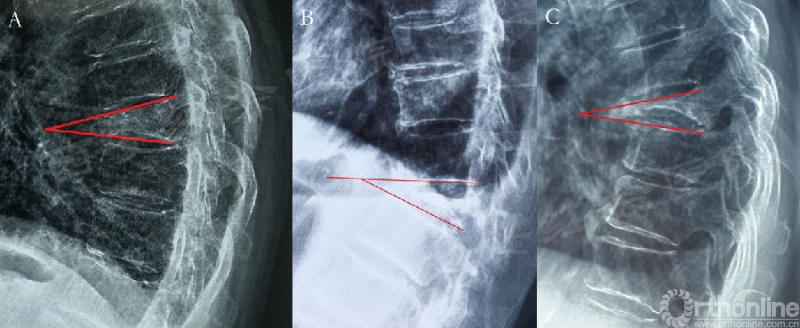

图3 椎体后凸角的测量方法

A.伤椎上下终版完整时测量上下终板延长线之间的角度(红线);B.当伤椎的上终板塌陷时,则选用上位椎体的下终板和伤椎的下终板延长线之间的角度(红线);C.当伤椎的下终板塌陷时,则选用下位椎体的上终板和伤椎的上终板延长线之间的角度(红线)